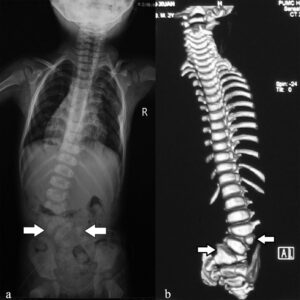

J Med Genet. 2016より引用

上手のような先天的な背骨の骨の奇形と変形が見られます。